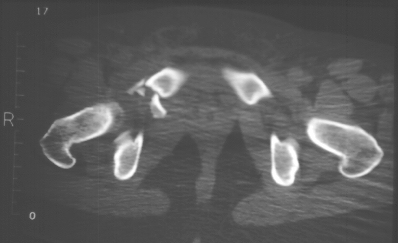

Radiographs:

Radiographs revealed a vertical buckle fracture of the right inferior sacrum, oblique fractures of the superior and inferior rami on the right and a fracture through the medial acetabulum. Obturator and iliac oblique inlet and outlet pelvic views, and a thin cut CT with 3-D reconstruction of the acetabulum were performed. These elucidated a comminuted anterior wall with fracture line extending to the posterior column. The posterior column was non-displaced. The pelvic fracture was non-displaced.

Assessment:

1. Right T-shaped acetabular fracture with anterior wall comminution.